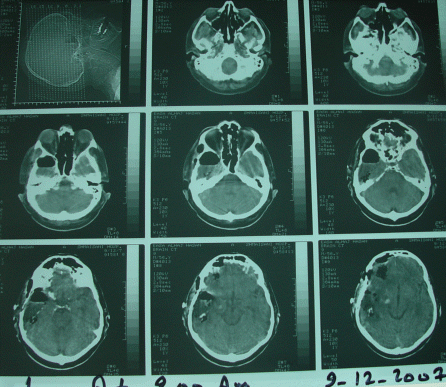

The patient in next postoperative day 09-December-2007 doing well and control CT-scan done showing the resection limits and the Gliadel wafers in the cavities.

The vital signs are stable and the patient using the T-piece with Venturi 50 and SO2 99% with pH 7.41 and pCO2 31 and pO2 97 mm Hg and he is convulsion free.